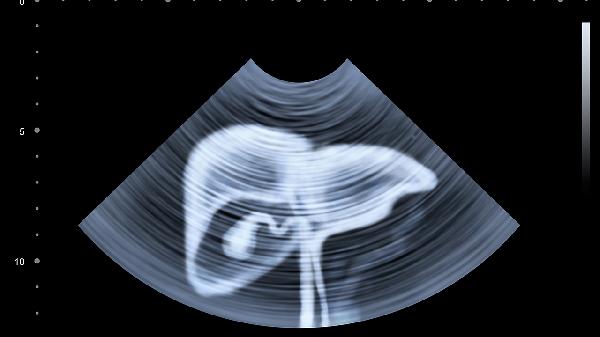

肝脏穿刺通常会有轻微疼痛感,但多数患者可以耐受。肝脏穿刺主要用于诊断肝脏疾病,如肝炎、肝硬化或肝脏肿瘤等。

肝脏穿刺过程中会进行局部麻醉,麻醉起效后穿刺部位的疼痛感会明显减轻。穿刺时可能会有短暂胀痛或牵拉感,类似打针时的轻微不适。穿刺后部分患者可能出现穿刺点隐痛,一般1-2天内会逐渐缓解。术后医生会密切观察患者情况,必要时给予止痛药物缓解不适。

进行肝脏穿刺前医生会详细评估患者凝血功能等指标,确保操作安全。穿刺后需卧床休息6-8小时,避免剧烈活动,观察有无出血倾向。保持穿刺部位清洁干燥,遵医嘱定期复查。合理饮食有助于肝脏修复,可适量摄入优质蛋白和维生素,避免油腻辛辣食物刺激。